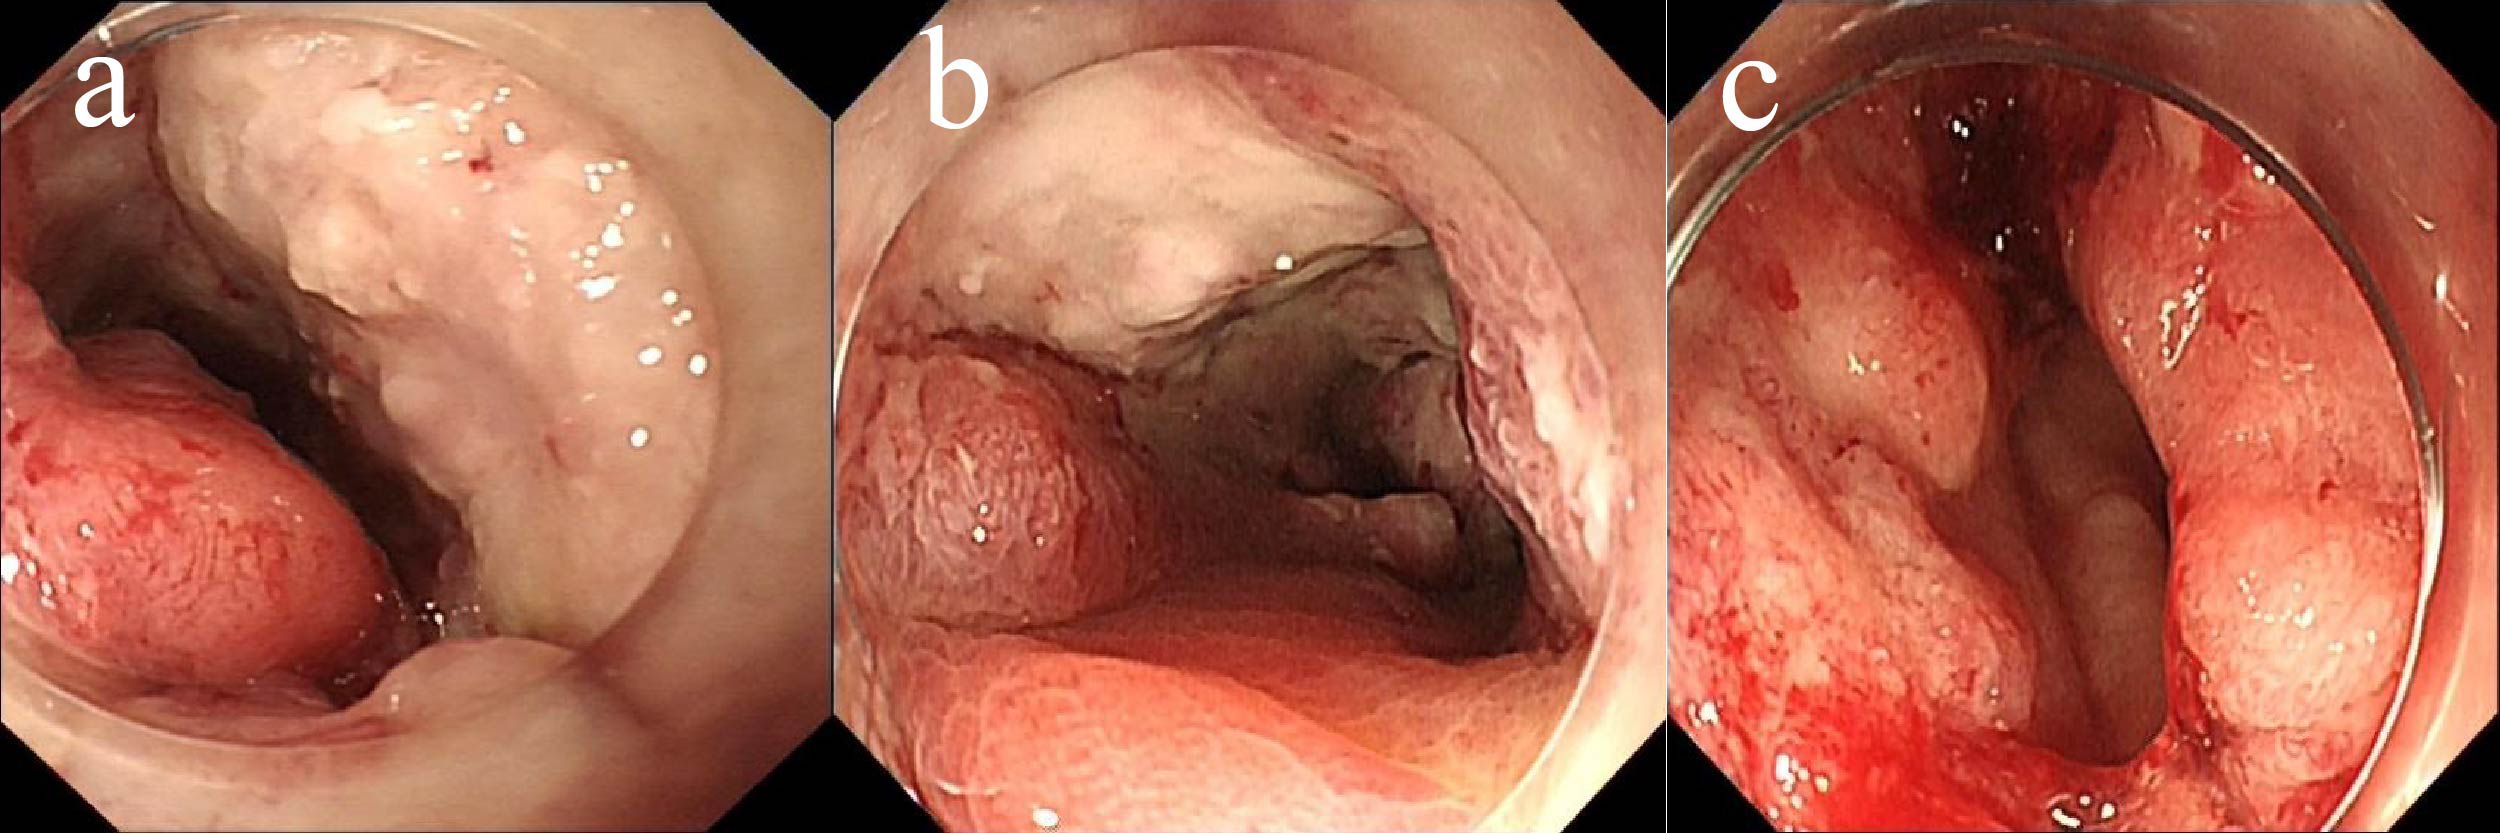

Gastric and colorectal cancers present significant therapeutic challenges, particularly in the elderly population, who often have comorbidities and diminished tolerance to standard treatments. This report describes an 85-year-old male with concurrent stage III gastric adenocarcinoma and stage IIIb microsatellite stable colorectal cancer, who declined both surgery and chemotherapy. Subsequently, the patient was treated with an innovative regimen consisting of endoscopic intratumoral injections of Oncolytic adenovirus H101 in combination with the PD-1 inhibitor tislelizumab. Following this combined therapeutic approach, the patient demonstrated notable tumor shrinkage and downstaging, accompanied by a reduction in serum tumor markers, including CEA and CA19-9. Additionally, there was an observed increase in CD8⁺ and CD4⁺ T-cell counts, indicating systemic immune activation. The treatment was well-tolerated, with the only reported adverse event being mild fever. The patient achieved nearly 4 months of progression-free survival and a substantial improvement in quality of life. This case highlights the potential of combining oncolytic virotherapy with PD-1 inhibition as a promising and novel personalized strategy for treating elderly patients with advanced gastrointestinal cancers who are unsuitable candidates for conventional therapies.